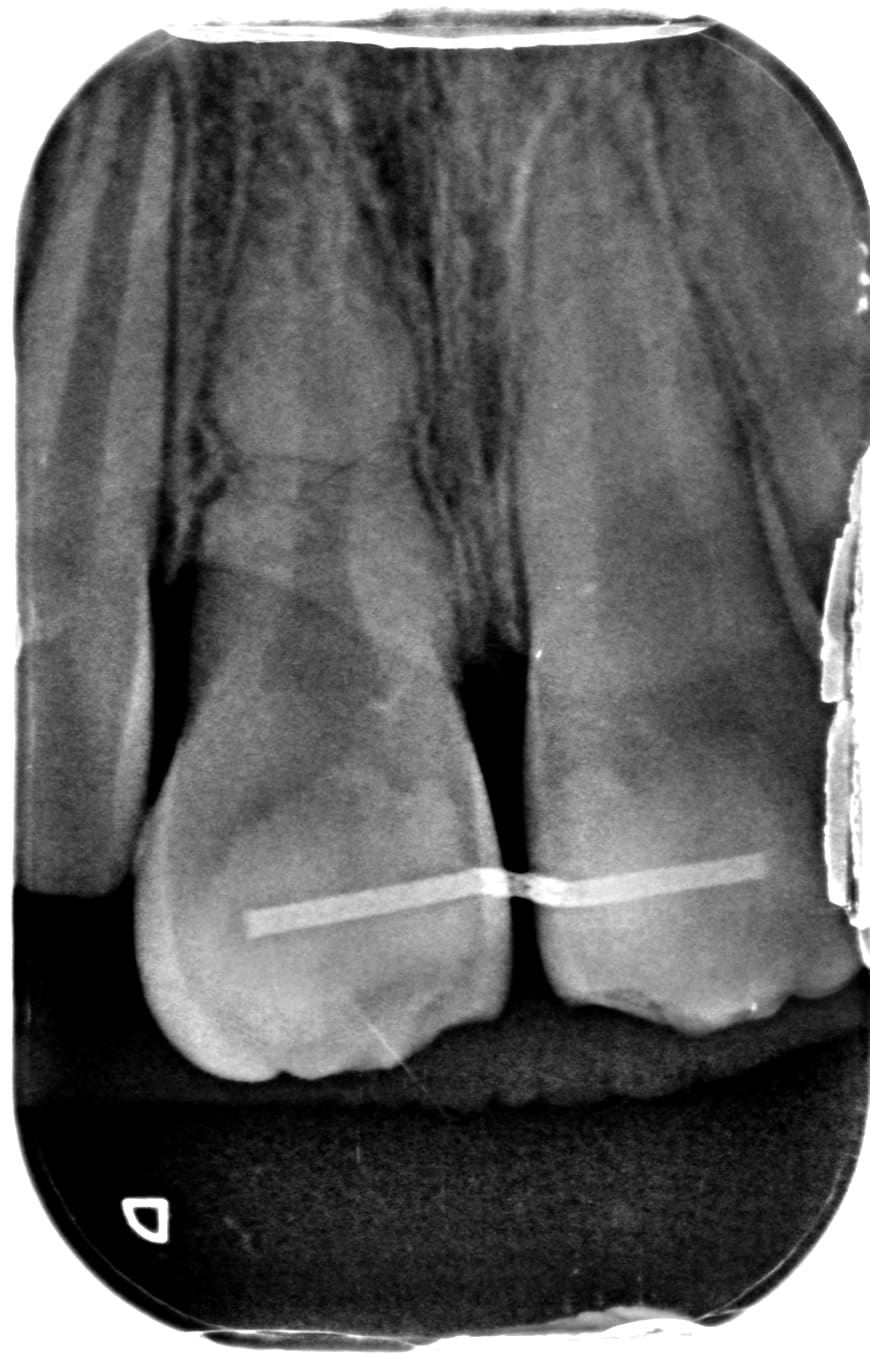

AVP chez un mineur il y a 2 jours, avec fracture amélo-dentinaire sans exposition pulpaire sur 11 et suspicion de fracture radiculaire sur 21.

Test au froid positif de 13 à 23.

Dans l'idéal, demande à l'ortho de poser une contention souple en urgence. Avec un peu de chance, tu peux viser le cal dentinaire sur 21.

Pour le reste, surtout, ABSTENTION et surveillance +++, et tu réévalues les volumes pulpaires dans un an. Si l'un des deux n'évolue plus, ça se finira en endo.

Contrôle à + 12mois.

Aucuns symptômes et une vitalité toujours présente sur le secteur.

Pas de mobilité ou de signes d'ankylose.